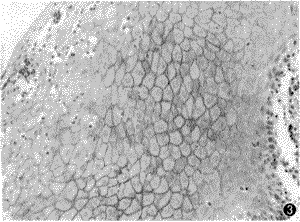

32例中25例为C-erbB-2阳性,占78% 。阴性对照未见染色。阳性染色见于上皮全层,主要位于棘细胞层,表现为细胞膜着色。细胞彼此相连,呈网状染色(图3),而基底层细胞染色浅,网状着色不明显。邻近微脓肿的上皮细胞一般为阴性。上皮单纯增生和异常增生的染色阳性率及强度未见明显差别。个别病例中可见异常增生细胞为阴性染色,而其表面形态与正常细胞相比则为阳性。对照组25例白斑的C-erbB-2染色有20例阳性,占80% ,阳性特点与念珠菌白斑相似。

图3 念珠菌白斑C-erbB-2,阳性染色主要见于棘细胞胞膜(SP×150)